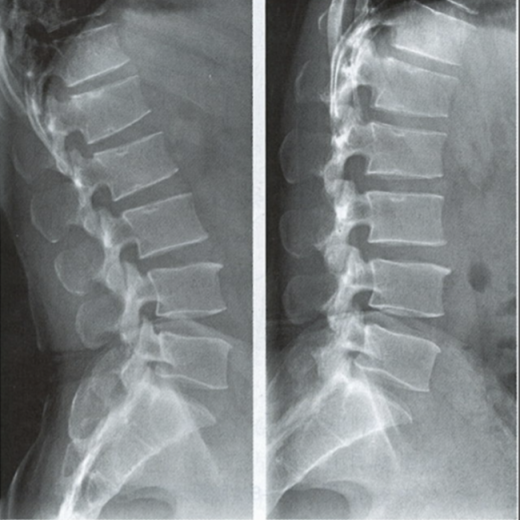

能屈能伸的腰椎——腰椎動力位

腰椎動力位,也稱為過屈過伸位,可以理解為兩個極限體位下的側位片,腰椎動力位通過做最大程度彎腰(過屈)和后仰(過伸)的動作拍攝側位片,來觀察腰椎在極限活動下的表現(xiàn)。如果說腰椎側位片能靜態(tài)體現(xiàn)椎體的解剖學結構、序列及生理曲度改變,那么腰椎動力位則是評估腰椎動態(tài)功能性的檢查。

腰椎過伸位:是指腰部盡可能向后伸展,以雙髖關節(jié)位支撐點,運動前后骨盆位置無改變。腰椎過伸時,向前的曲度大于生理曲度,上部向后傾斜。

腰椎過屈位:是指腰部盡可能向前彎曲,以雙側髖關節(jié)位支撐點,運動前后骨盆位置無改變。腰椎過屈的表現(xiàn)位向前的曲度減小、變直,上部向前傾斜。

當1度及以上的滑脫時才可以在普通腰椎側位上觀察到,而1度以下的滑脫或失穩(wěn)則在普通側位片上難以發(fā)現(xiàn),這時候就需要借助腰椎動力位進行診斷。

腰椎動力位 左圖為過伸位、右圖為過屈位